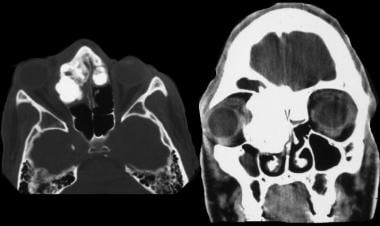

2 superior orbital fissure. Ct is superior to mri for subtle cortical bone changes but marrow processes are best characterized with non gadolinium gd contrast enhanced t1 mri. For lesions that are completely intraosseous the mass may only be appreciated on mri figure 1.

The base of the skull is perforated by numerous foramina which allow vessels and nerves to pass through the base of the skull allowing the intracranial cavity to communicate with the rest of the body see main article. Skull ct anatomy the sagittal suture is the line where the right and left parietal bone are in contact. A noncontrast sinus or skull base ct which covers the mastoids temporal bone and entire skull base is recommended and intravenous contrast is not usually necessary as the mri will provide soft tissue detail.

Ct is more sensitive in detecting fibro osseous skull base lesions calcification and sclerosis. The module interface is meant to mimic a radiology workstation with adjacent image scrolling via arrow keys and or mouse wheel button. Navigating the skull base identify the petro occipital fissure to navigate the major structures of the skull base.